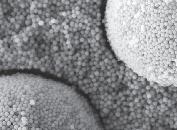

FARVE FRA LYSET UENDELIGT MANGE MULIGHEDER

Kan tydeligt ses på SEM-billedet: Perlestrukturen i OMNICHROMA sammenlignet med konventionelt knuste partikler.

Bis-GMA-fri formel: for bedre biokompatibilitet

Enkel lagerføring: blot 1 farve er nok til økonomisk bæredygtighed

Smart Chromatic Technology –1.000 hvide farver

Strukturelle farvenuancer uden kunstige farvepigmenter: tilpasser sig uden problemer til enhver tandfarve fra A1 til D4